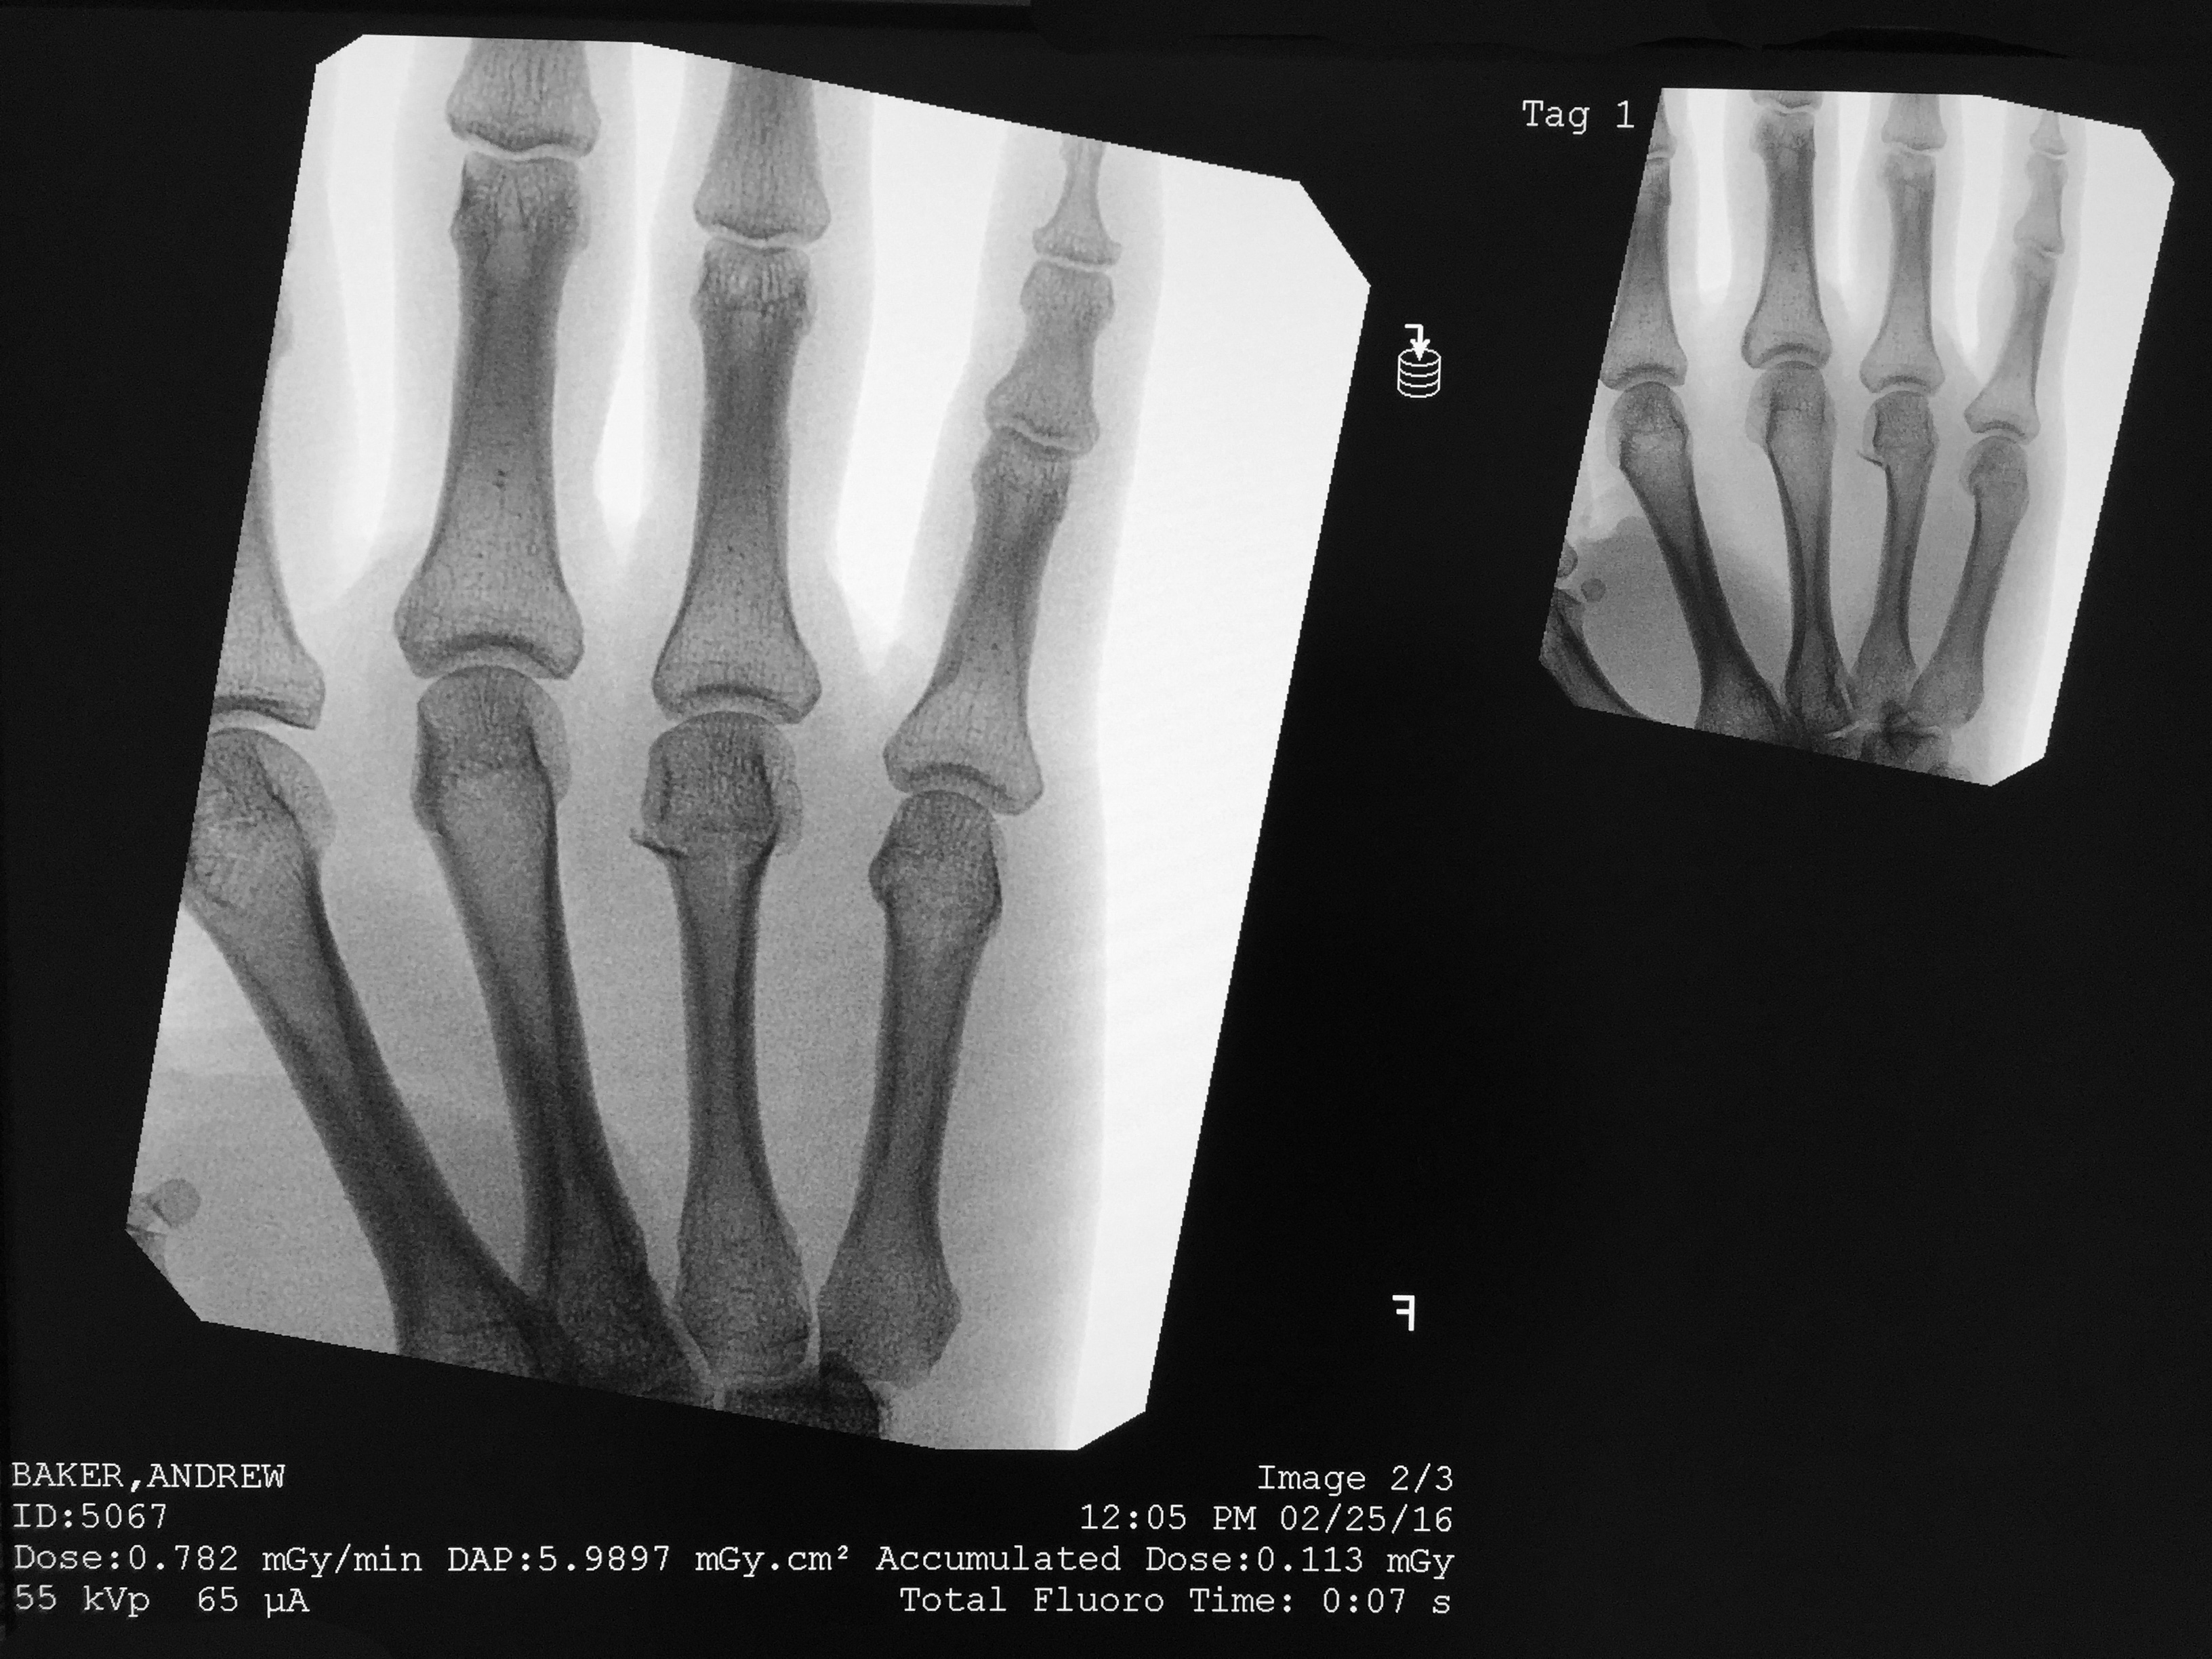

The little sliver on the ring finger, below the knuckle.  Hairline fracture.  Gonna kill my bouldering for a month.

fracture